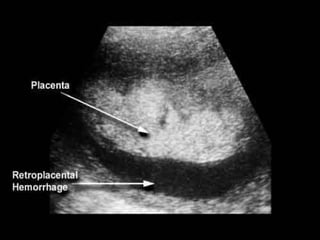

Placental Abruption

Placenta separates from

uterine wall

Painful dark or clotted blood

Risks: HTN, smoking, ETOH,

cocaine, multiparity,

previous abruption,

trauma, mom > 40

Management: U/S, Ob

consult, cardiac/fetal

monitoring, IV, pre-op labs,

delivery if possible